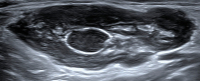

Abbildung 1: Normalbefund zervikal. Diesen kennzeichnet eine scharfe Begrenzung, ein echoreicher Hilus, eine gleichmäßige Breite des Kortex, eine reguläre Größe und ovale Form.